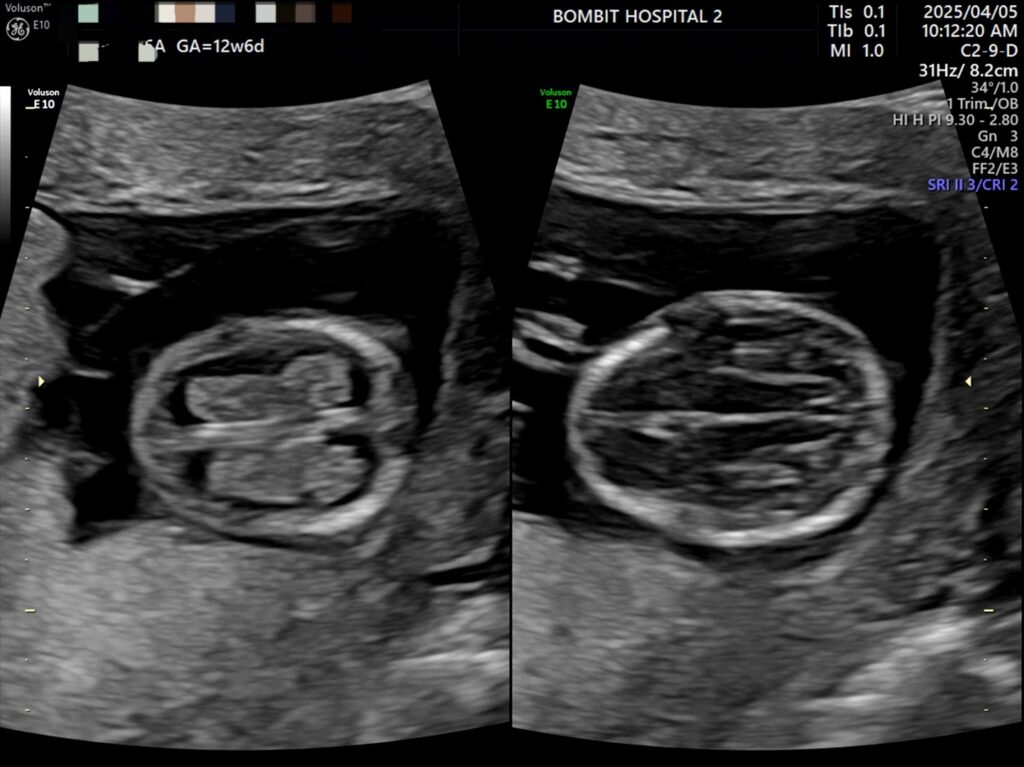

봄빛병원에 다시 방문. 정밀초음파도 하고, 다시 진료도 보았다.

피고임은 이제 없어졌다고 했다. 약간은 느려진 듯한 심장소리도 다시 들었고 니프티 검사용 채혈도 했다.

정밀초음파 사진.